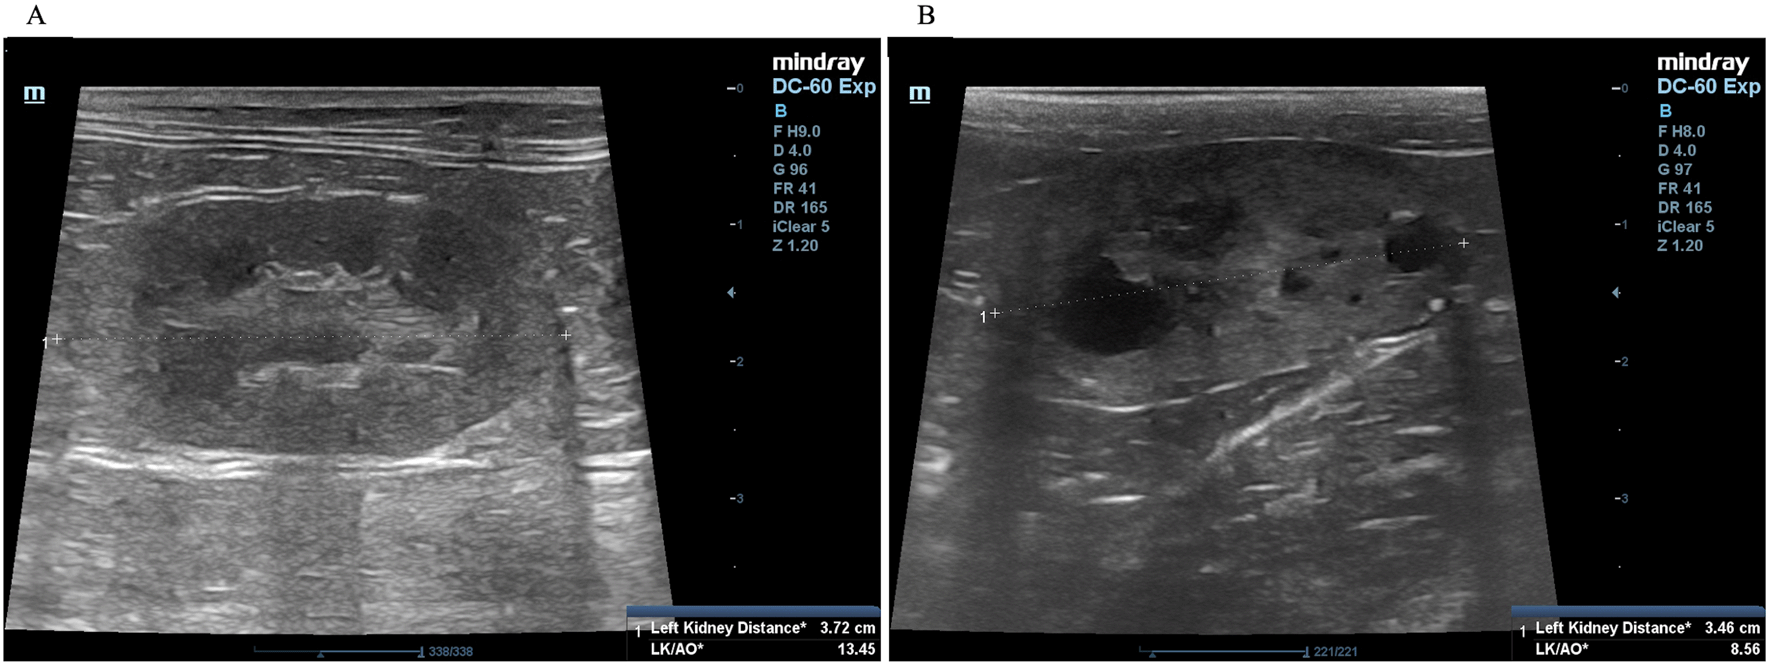

A complete blood count and serum biochemistry profile were performed for each cat. Kidney characterization was assessed by ultrasonography analysis in all cats using only gentle restraint and no sedation. The non-invasive two-dimensional (2D)-mode ultrasonography was used to define the kidney structure and size. The ultrasonography images have demonstrated that multiple cysts are a common finding in PKD1 heterozygous mutation cats, as shown in Figure 2.

The procedure for ultrasound examination of the kidneys followed that of a previous report.4,20 Briefly, ultrasonography was performed using a Mindray real-time ultrasound machine (model DC-7, Shenzhen Mindray Bio-medical Electronics, Nanshan, Shenzhen, China) with a linear transducer (frequency 7.5-12.0 MHz). The kidneys were examined in the longitudinal and transverse planes. Results were recorded for each cat. The three separated regions, the renal cortex, the renal medulla, and the renal sinus, were identified. The renal sinus is the most hyperechoic component of the kidney and is surrounded by the renal pelvis and vascular branches. In the renal pelvis, ultrasonography images can be assessed using the renal crest as a landmark. The renal size can be measured by measuring from the long axis view. The renal lengths of the right and left kidneys were measured to identify the renal structure, as shown in Figure 2.